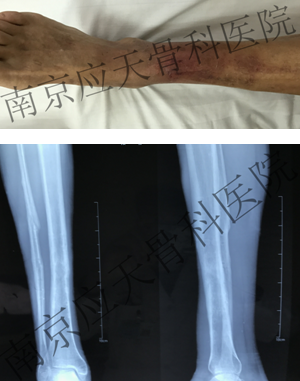

患者安徽池州居民,于2019年11月份无明显诱因始出现右小腿远端出现红肿,伴有疼痛,持续性加重,偶有发热,休息后无好转,就诊于当地医院,行抗感染等保守治疗,效果一般,当地医院建议转上级医院继续治疗,患者为求进一步诊治来我院就诊。

术前: